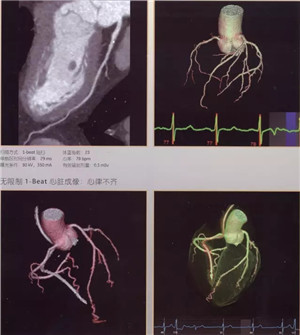

日前,辽阳市中心医院引进当今医学界最先进超高端的美国GE公司生产的Revolution CT(512层)正式投入使用,以此为标志,我市医学影像诊断技术进入超高清时代。该CT是当今世界上临床性能最为强大的CT,它以“合三为一、集大成”的特点引领着CT扫描领域在能谱、速度、宽度方面的国际潮流。落户于中心医院的该CT设备,是东北第三台,辽宁省第二台,目前中国医科大学附属第一医院、盛京医院尚无此种设备。

512层Revolution CT是目前业内探测器最宽、扫描速度超快、射线剂量超低、图像超清晰,且能进行能谱成像的后超高端CT,被称为“革命性”的CT。它实现了——

扫描速度超快:仅需0.28秒,不受心率快慢限制,只需一个心跳即完成精准的心脏CT检查,成为无创确诊冠心病的最佳检查手段。